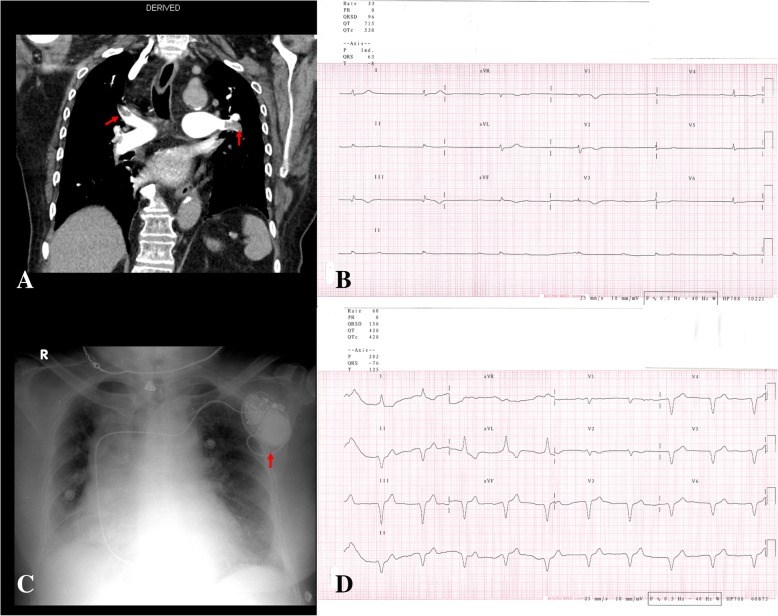

Background: Pulmonary embolism (PE) is a fatal condition, with a subsequent variety of complications. Although rare, the ensuing presentation of atrial fibrillation (AF) secondary to PE is evident in the literature. However, there has been no report of AF with slow ventricular response requiring a pacemaker as a complication of PE.

Case presentation: A 78-year-old obese female presented to the emergency room with new onset dyspnea. Computed tomography pulmonary angiogram revealed bilateral PE. Twenty-four hours later, the patient developed new onset AF with slow ventricular response. Therefore, a single chamber pacemaker was implanted.